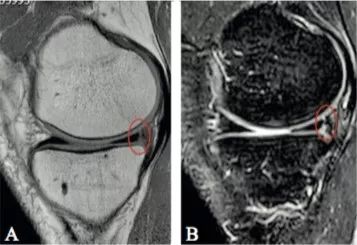

Hash等指出,Ramp损伤在MRI上的最突出 标志是在内侧半月板后角与后内侧关节囊之间插入了一个薄层的液体信号,观察内侧半月板后角与滑膜分离征象。

病例图片(均来自网络):